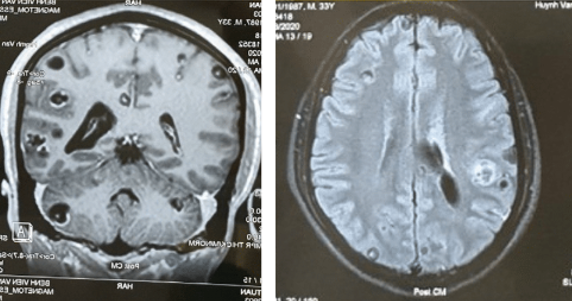

Đau đầu kèm co giật toàn cơ thể trong vòng 01 tháng ở bệnh nhân nam 31 tuổi, có thói quen ăn thịt tái, sống, được chẩn đoán sán não